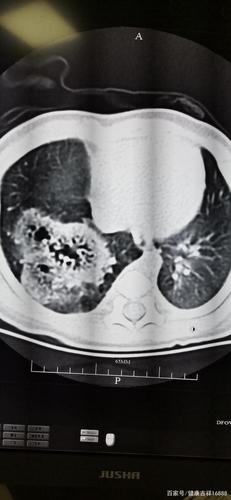

肺囊腺瘤:今天遇到一个罕见病例给大家分享一下!

先天性肺囊腺瘤